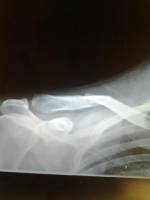

The picture you are looking at is of Felipe's broke clavicle, known colloquially as the collar bone. Felipe planned on racing in the Wolfpack Midnight

Drag Race but obviously he cannot race under the circumstances. So he decided as a way to promote his company, Famli Straps and to hook